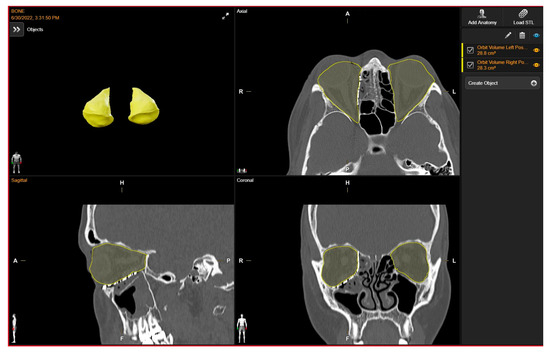

Orbital volume measurements of both the reconstructed and unaffected orbits were conducted using a dedicated tool for orbital volume measurement integrated into the software suite “Brainlab Elements Contouring”, version 4.0 (Brainlab, Feldkirchen, Germany). To maintain measurement integrity and minimize potential bias, we relied on the automatically generated volumes produced by the software. Given the precision and specialized functionality of this tool within the Brainlab portfolio, we considered the automatically generated volumes to be robust and indicative of the true orbital volumes. By calculating boundaries on presurgical CT scans, the software’s algorithms incorporate anatomical landmarks and contours, ensuring accurate delineation even in cases of anatomical variation or pathology, without the need for manual adjustments.

Through utilization of the automated volumes generated by the Brainlab software, our objective was to reduce potential bias and ensure consistency in measurements, thereby enhancing the reliability of our findings.

The volume of the unaffected contralateral orbit serves as a reference for comparison. Subsequently, the volume discrepancy between the reconstructed and contralateral orbits was computed (Figure 3).

Figure 3. Post- operative Orbital Volume Measurements.